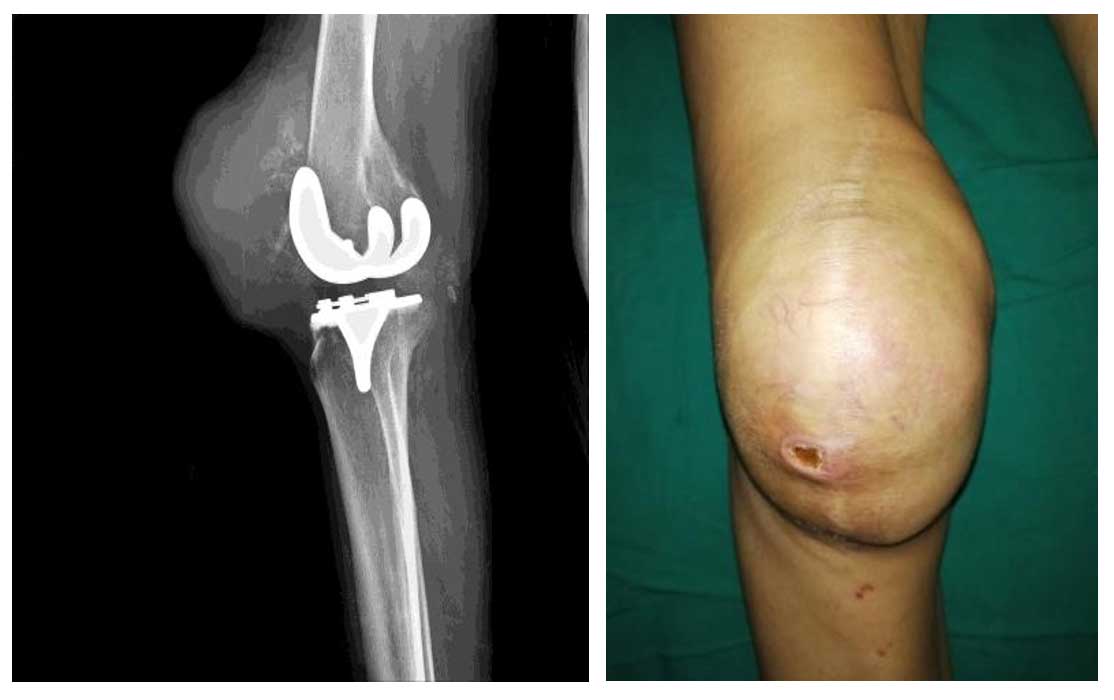

72 yaş erkek hasta, Hemanjioperisitoma tanısı ile aktif tedavi görmekte olup geçmişte diz protezi ameliyatı öyküsü bulunmaktadır. Hasta yaklaşık 4 aydır devam eden, giderek artan ve yürüme güçlüğüne neden olan diz önü ağrısı ve belirgin şişlik şikayetleri ile başvurdu.

Yapılan görüntülemelerde diz kapağında (patella) metastaza bağlı ileri düzey kemik harabiyeti saptanmıştır. Mevcut yıkım nedeniyle patellanın fonksiyonunu sürdüremeyecek durumda olduğu görülmüştür.

Ameliyat Öncesi: Röntgende diz kapağında ciddi harabiyet ve protez varlığı. Klinik olarak diz önünde şişlik.